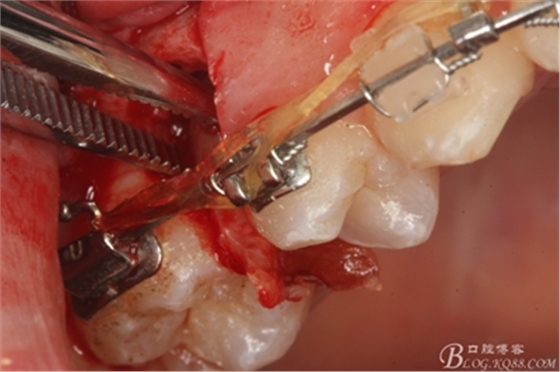

圖13. 用小球鉆去除約1mm牙槽骨,暴露15牙根面約5mm。

圖14.用小球鉆縱分15牙根